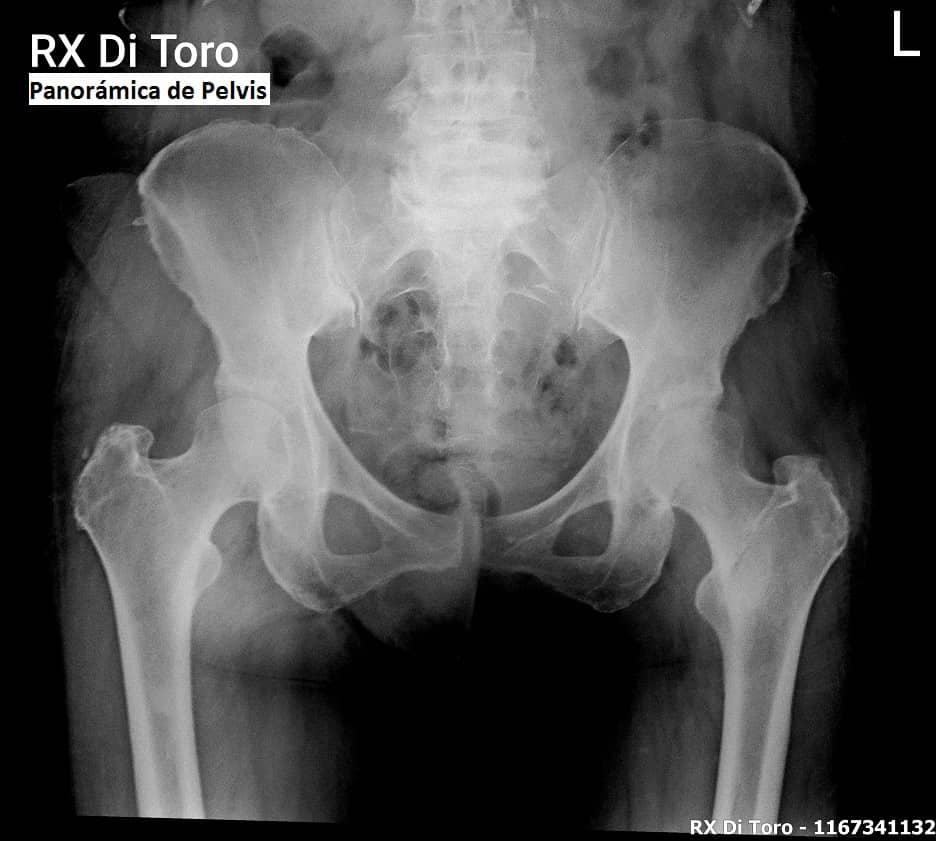

Utilizamos sensores Flat Panel, que nos permiten acortar al Máximo el tiempo de exposición (Dosis de Radiación) y obtener la adquisición inmediata de las imágenes.